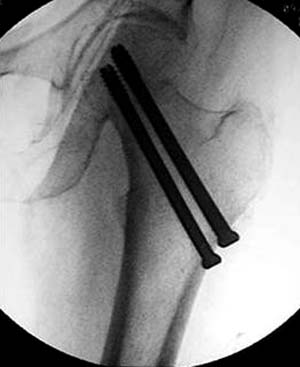

Правильная техника фиксации - это три параллельных  каннюлированных винта под углом 130 -135 градусов к диафизу, не ниже уровня малого вертеля. Проведенные ниже вертела винты с бОльшим углом (более вертикальные) в 20% осложнялись подвертельными переломами бедра. Ближе к кортикальному слою винты с длинным контактом резбовой части, а также каннюлирванные механически лучше, чем сплошные. Расположение винтово - в  в виде V т.е. один внизу по калькару и два сверху-спереди и сзади.

Для убедительности здесь пример подвертельного перелома после 3 недели, где латеральный кортекс ослаблен еще и из-за неоднократных попыток введения шурупов.